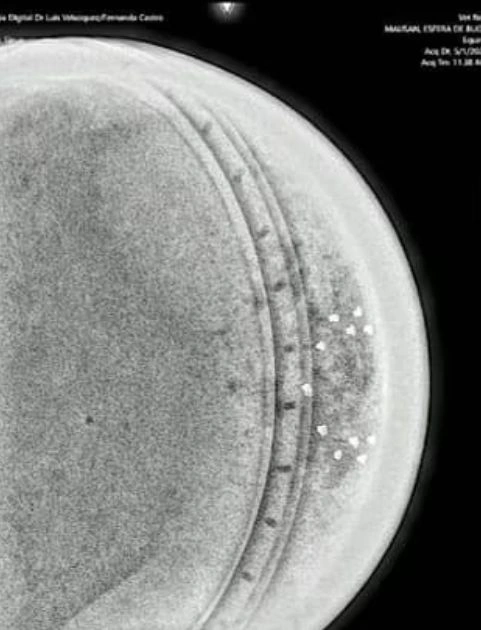

Phân tích X-quang cho thấy cấu trúc bên trong tinh vi, gồm 3 lớp kim loại, một “chip” trung tâm và 18 điểm nhỏ sắp xếp có chủ đích – điều không phổ biến trong công nghệ nhân loại.(Ảnh: Daily Mail)

Không có dấu hiệu hàn nối, vật liệu có độ đặc giống xương người, càng làm dấy lên nghi vấn về nguồn gốc ngoài hành tinh.(Ảnh: Daily Mail)